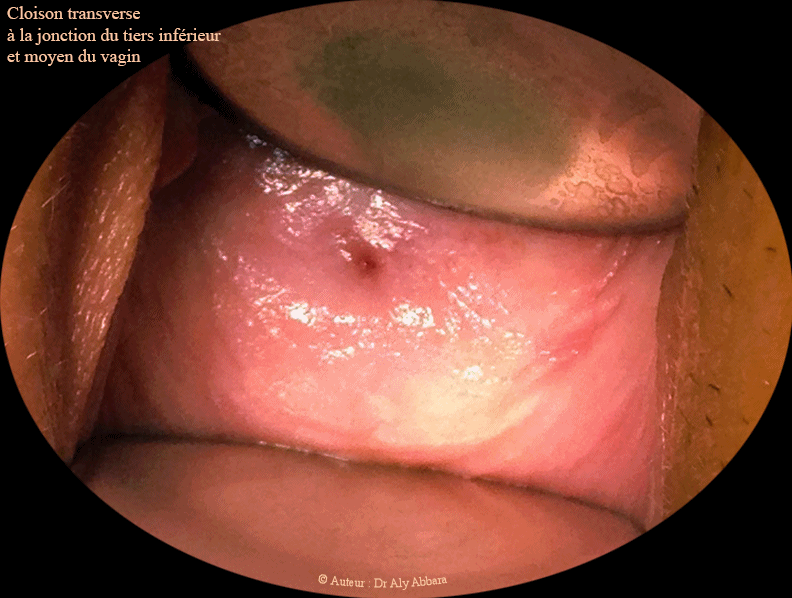

• Images échographiques et cliniques animées mettant en évidence la présence d'une cloison vaginale transversale située au niveau de la jonction du tiers inférieur avec le tiers moyen du vagin.

• Cette cloison vaginale est de 3 à 4 mm d'épaisseur ; elle divise transversalement le vagin en deux compartiments :

• La cloison vaginale transversale est quasi complète à part la présence d'un pertuis millimétrique dans son centre permettant une évacuation très partielle du sang menstruel vers le vagin bas.